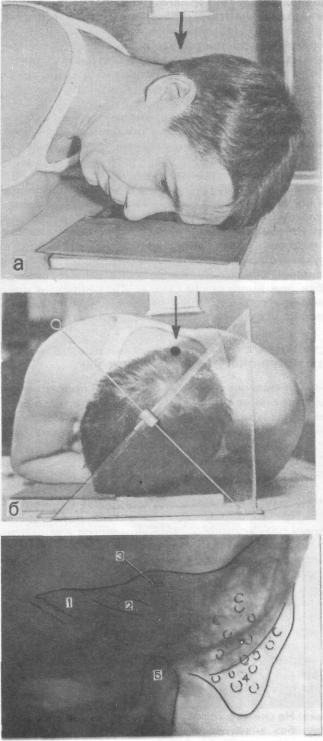

Анатомия сосцевидного отростка